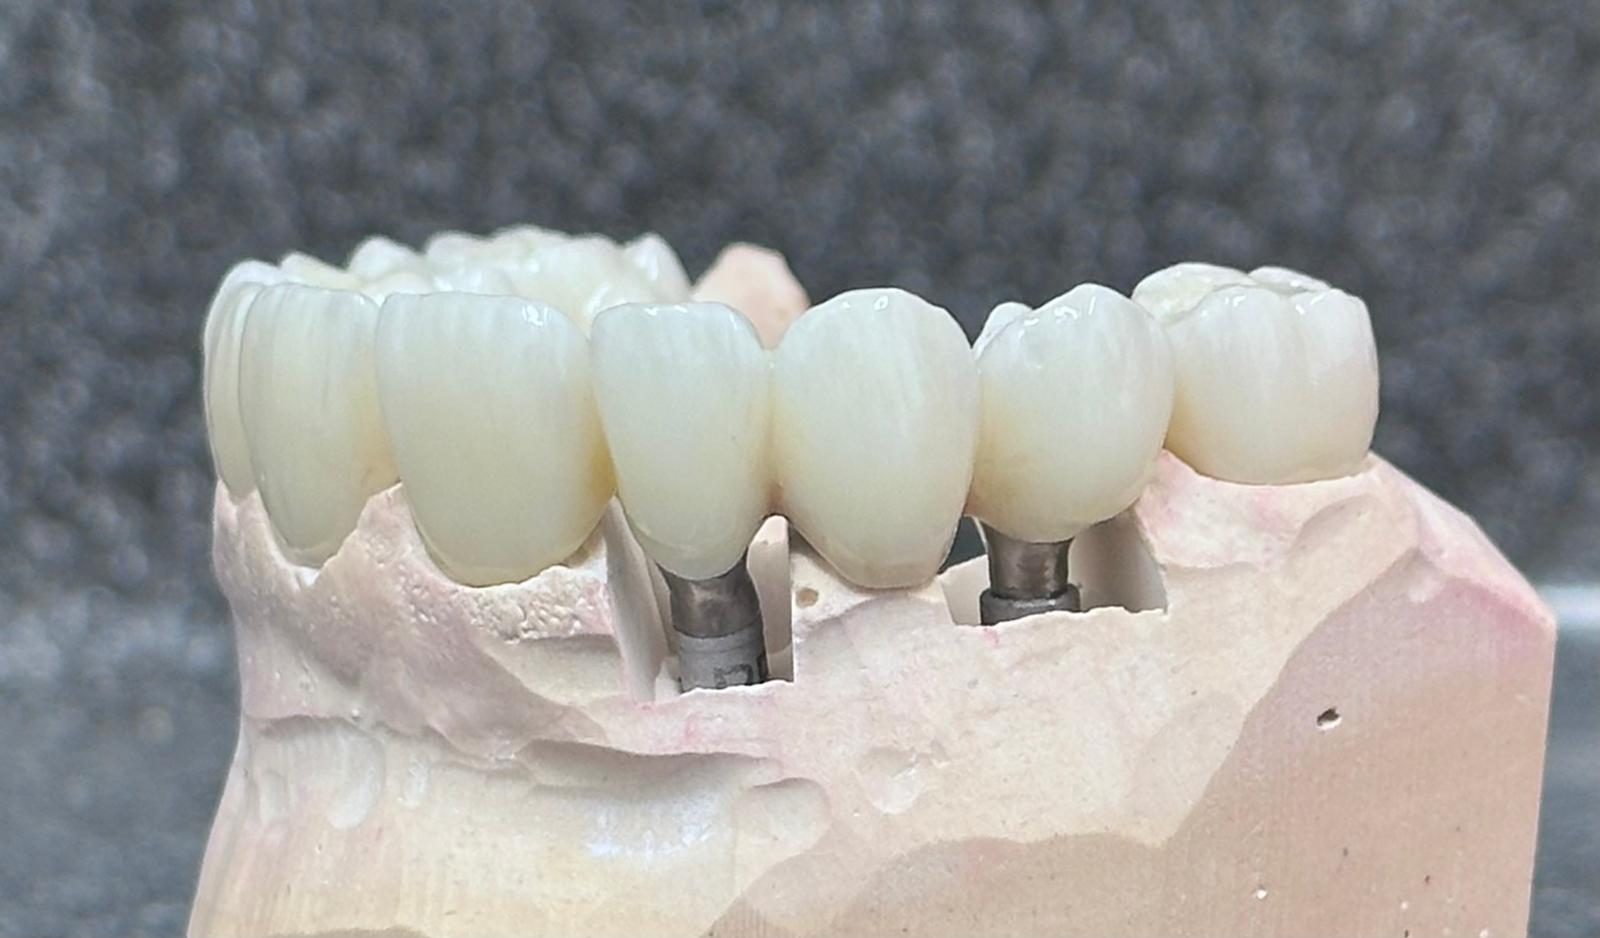

Implants placed using a digitally planned stackable surgical guide following alveolectomy, ensuring ideal positioning and a stable foundation for full-arch restoration.

Full smile rehabilitation involving replacement of missing and failing teeth with implant-supported restorations, combined with aesthetic correction of existing dentition. The treatment was carefully planned to restore function, improve alignment, and achieve a balanced, natural-looking smile.

Implants were strategically placed to support long-term stability, with particular attention to soft tissue contours and emergence profiles to ensure seamless integration with the surrounding teeth. The final restoration was designed to enhance both aesthetics and bite function, delivering a confident and harmonious result.